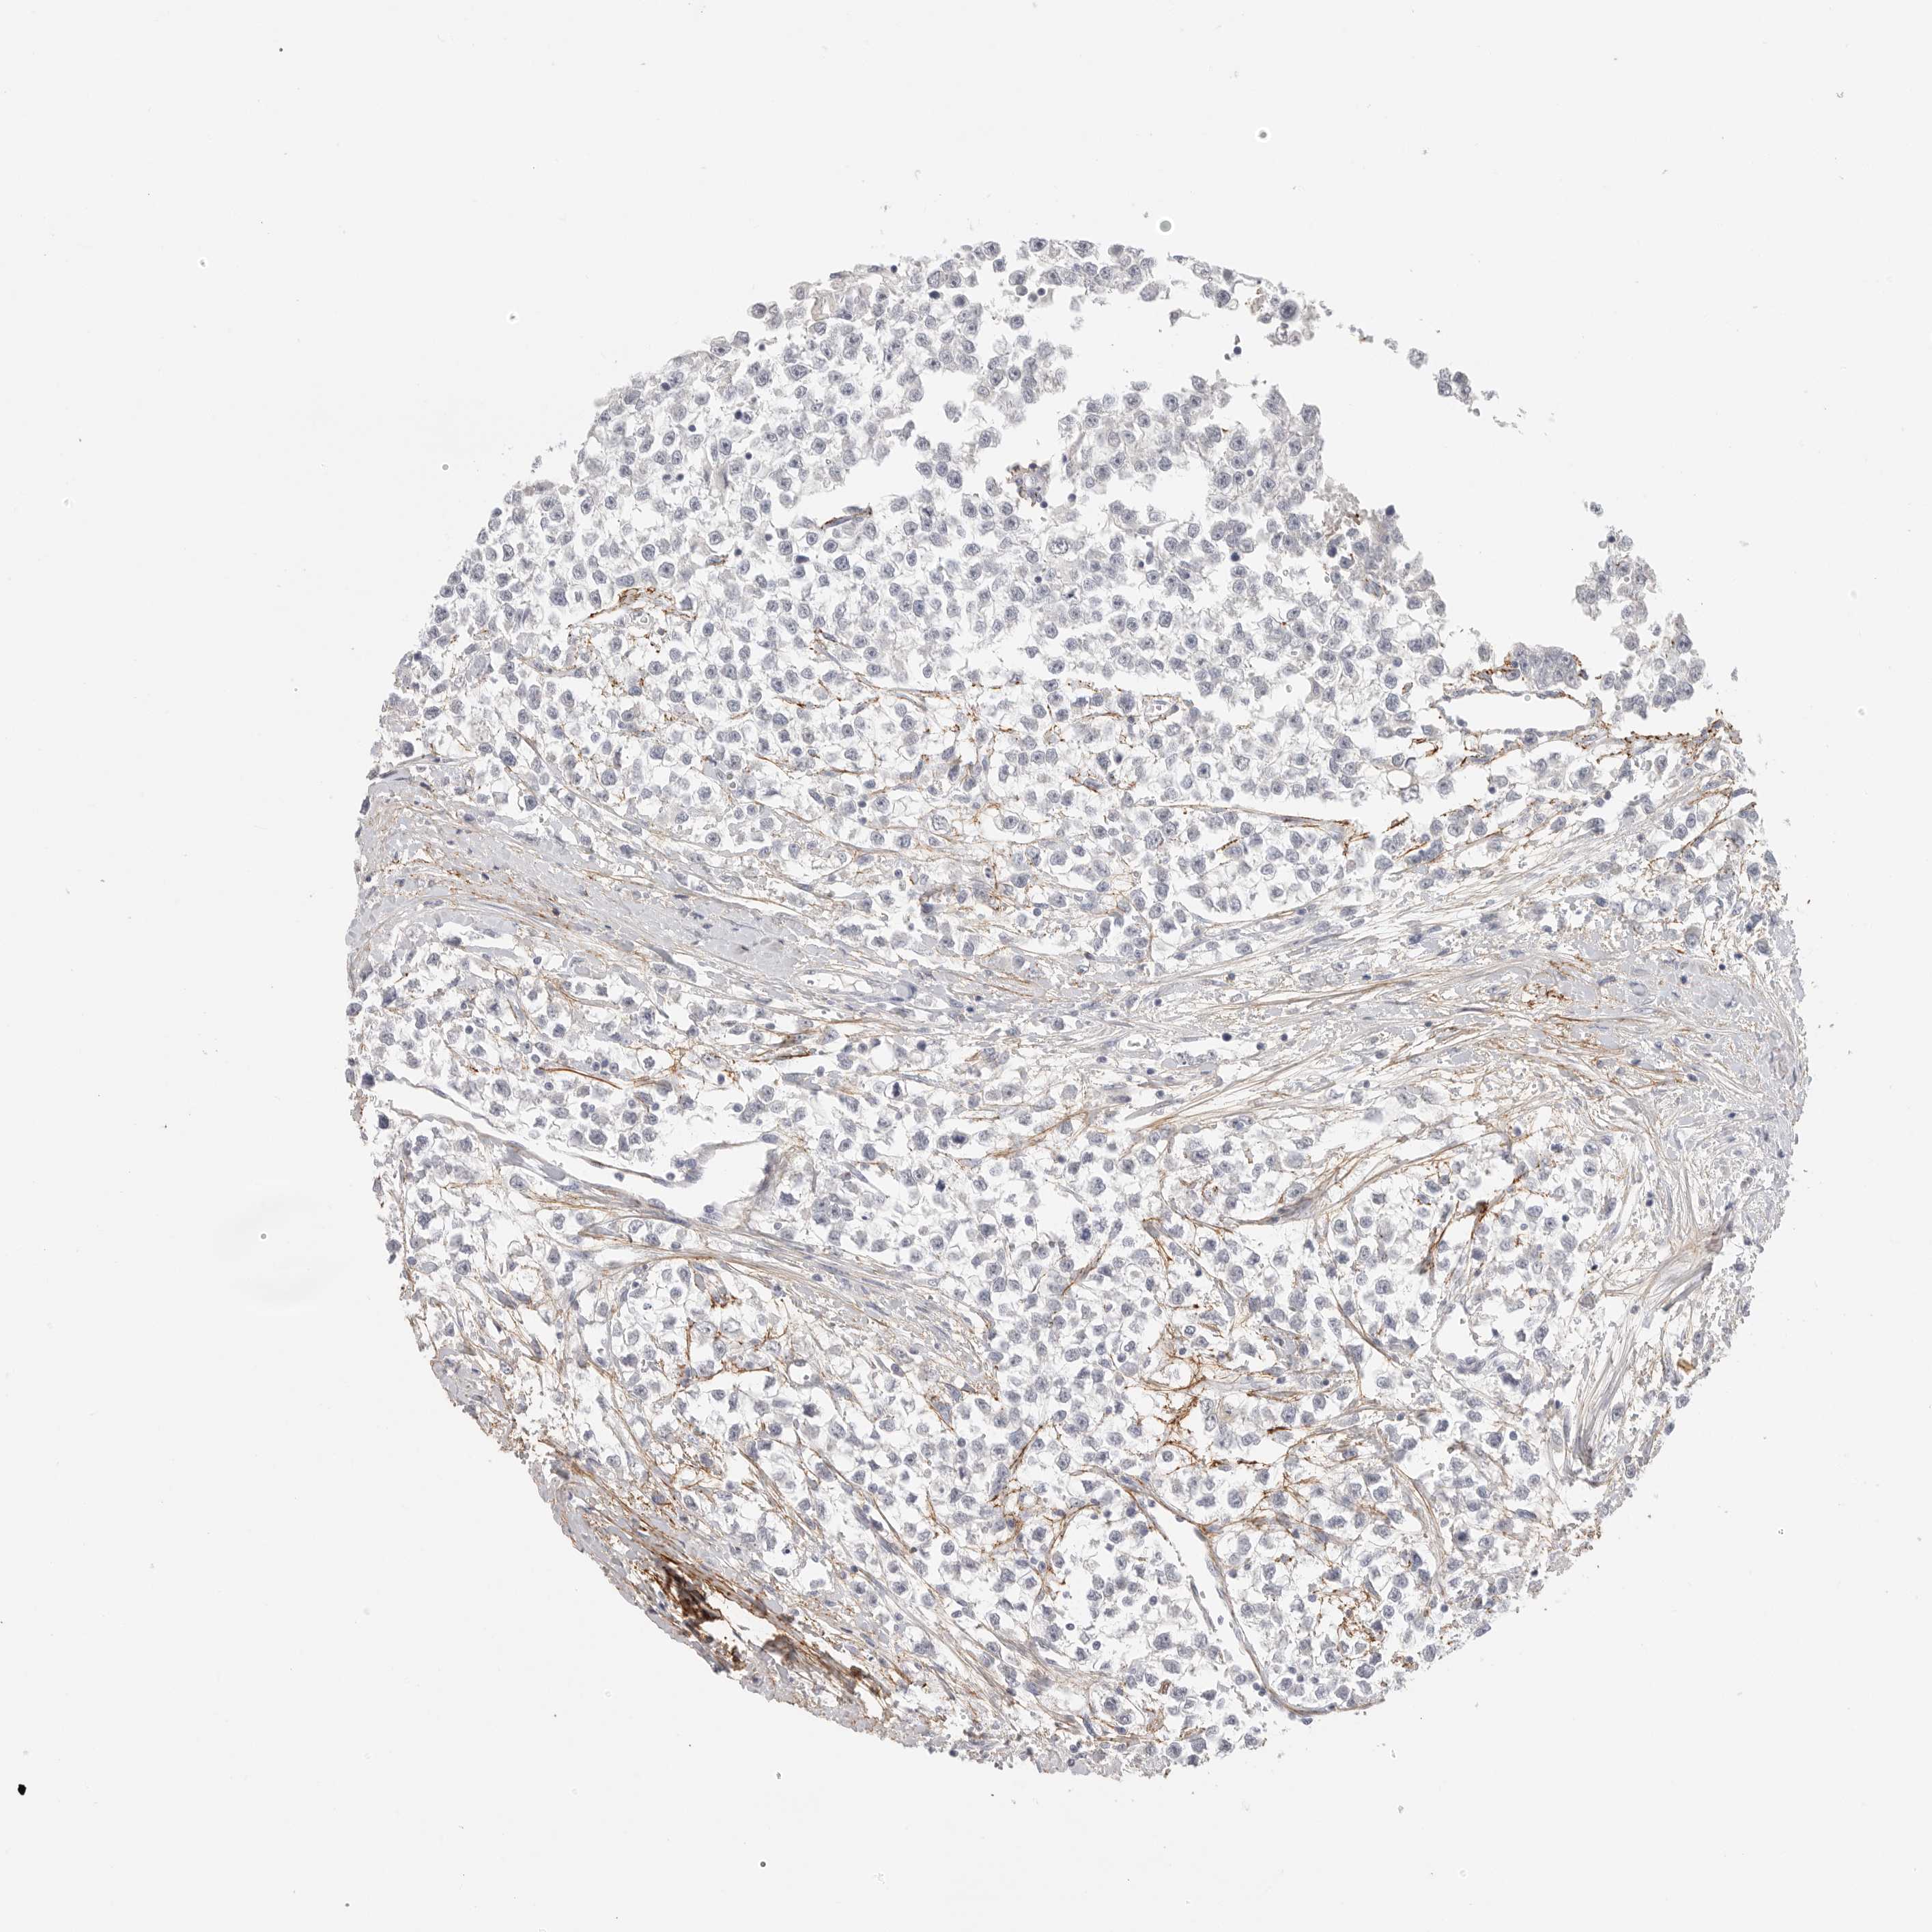

TESTIS CANCER - Protein expressioni

A mouse-over function shows sample information and annotation data. Click on an image to view it in a full screen mode. Samples can be filtered based on level of antibody staining by selecting one or several of the following categories: high, medium, low and not detected. The assay and annotation is described here.

Note that samples used for immunohistochemistry by the Human Protein Atlas do not correspond to samples in the TCGA dataset.

Antibody stainingi

Antibody staining in the annotated cell types in the current human tissue is reported as not detected, low, medium, or high, based on conventional immunohistochemistry profiling in selected tissues. This score is based on the combination of the staining intensity and fraction of stained cells.

Each image is clickable and will lead to virtual microscopy that enables deeper exploration of all samples and also displays staining intensity scores, fraction scores and subcellular localization as well as patient and tissue information for each sample.

Antibody HPA012853

Antibody CAB026401

Staining

High

Medium

Low

Not detected

Intensity

Strong

Moderate

Weak

Negative

Quantity

>75%

75%-25%

<25%

None

Location

Nuclear

Cytoplasmic/membranous

Cytoplasmic/membranous,nuclear

Carcinoma, Embryonal, NOS

Seminoma, NOS